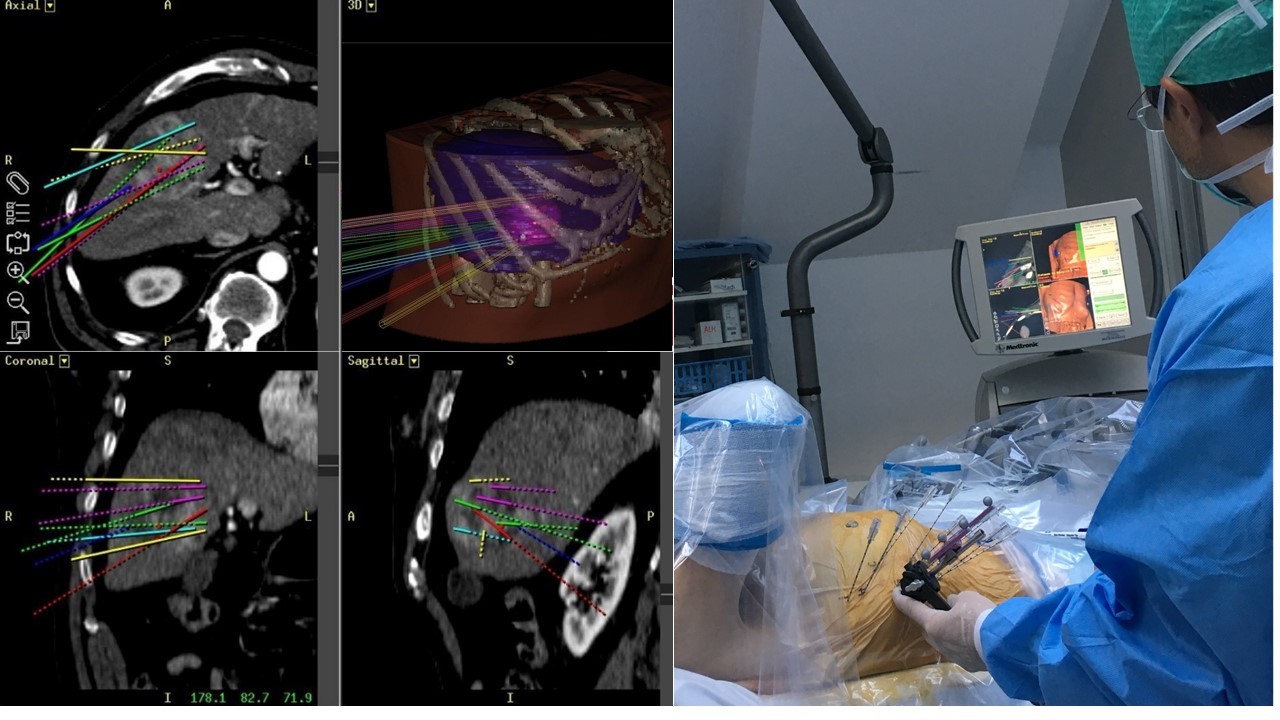

In 2001 we performed the first in man "stereotactic radiofrequency ablation (SRFA)" of a liver tumor 1 by introducing the stereotactic planning, image fusion and guidance principles into the field of thermal ablation. In contrast to the conventional "freehand" single-probe technique multiple probe positions are planned on 3D image datasets in order to cover the tumor by overlapping ablation zones. The whole procedure is performed under general anesthesia using muscle paralysis and respiratory triggering. An optical navigation system is used to adjust an aiming device for precise coaxial needle placement. Up to three radiofrequency electrodes are introduced through the coaxial needles for serial tumor ablation. Immediate fusion of the post ablation contrast-enhanced CT with the planning CT allows for rapid reliable intraoperative assessment of the result.

Figure 1A: Breast cancer liver metastasis with 9 cm in left liver lobe.

Figure 1B: Control CT with 15 coaxial needles in place.

In the meantime, we have treated > 900 patients with > 3000 liver tumors in > 1500 sessions and collected them in our prospective SRFA registry. After bridging therapy with SRFA for liver transplantation, complete histopathological response was found in 183 of 188 treated lesions (97.3%) and in 50 of 52 lesions > 3cm (96.2%) 2. In a recent paper reporting the results after SRFA of very large tumors (> 8 cm) 3 (Figure 1) and in other studies including primary and secondary liver tumors the short- and long-term outcomes after SRFA were comparable to HR.

The current study answers the question (which was already raised in 2002 after presentation of the method and the initial experiences in the first 15 patients), whether the increased complexity of SRFA with placement of multiple coaxial needles (median: 6, range: 1- 50) per session for the treatment of multiple tumors (median: 1, range: 1-18) and large tumors (median: 2.6 cm, range: 1- 18 cm) might affect the post-procedure health-related quality of life (HRQoL). In addition, the results of the post-procedure HRQoL after liver SRFA were compared to other concurrent treatments, such as transarterial chemoembolization (TACE), systemic chemotherapy or hepatic resection.